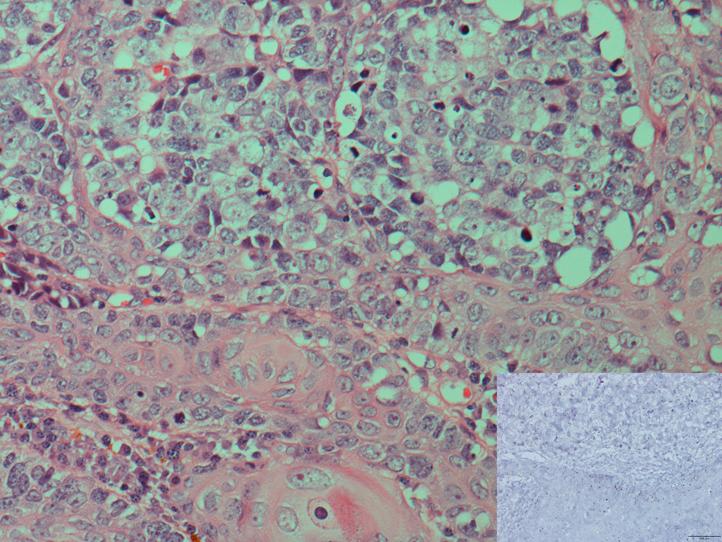

Combined squamous cell carcinoma and Merkel cell carcinoma of the vulva: Role of human papillomavirus and Merkel cell polyomavirus.

https://cdn.ncbi.nlm.nih.gov/pmc/blobs/8932/4808721/64c7e3f91602/gr1.jpg